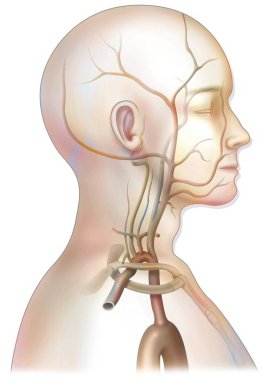

The arterial blood supply to the neck (carotids and vertebral arteries).

İnsanBaşıkanİlaçyüzboğazıBoyunresim çalışmasıprofilNormalbeyinarterkarotidKan damarıKan dolaşımıİnsan AnatomisiSerebral kan dolaşımıvaskülarizasyonsubclavian arteryortak Karotis arterbrachiocephalic Arteryel gövdeVertebral arterfacial arteryserebral artercervical arterytemporal arterydahili şah damarıharici şah damarıdeep cervical arteryBenzer İçerikler